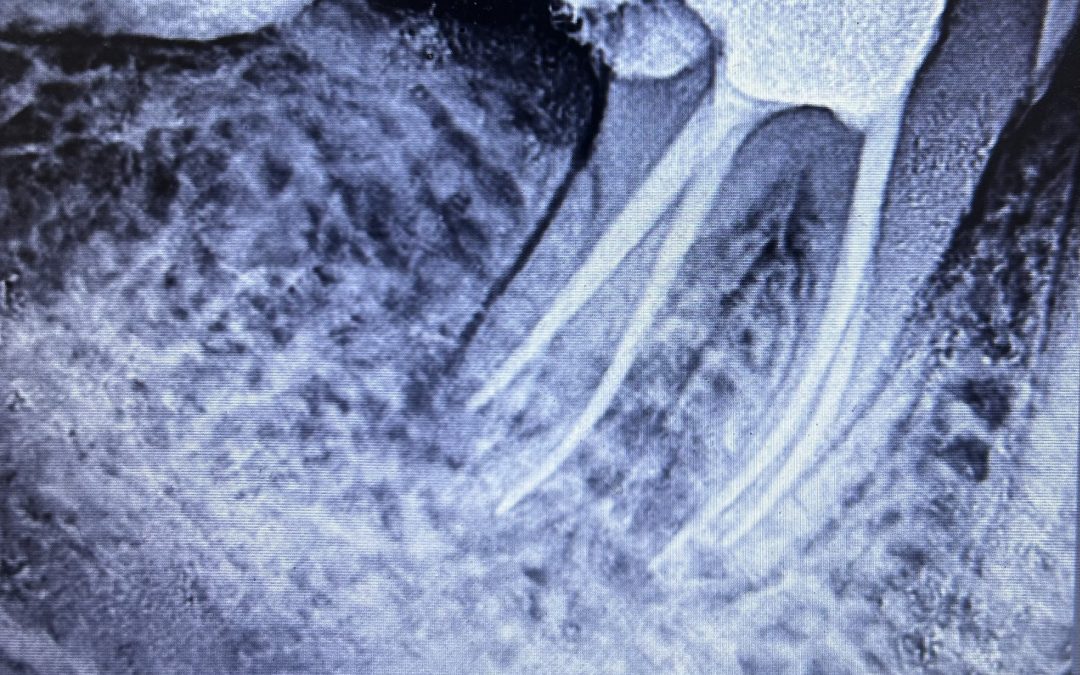

“Can you save it? I really don’t want to lose my tooth.” Dr. Chelja Ram stared at the panoramic X-ray, her brow furrowed. The patient, a young man named Selvam, was sitting opposite her, his face pale and drawn. Selvam’s lower molar was...

The Root of the Matter Dr. Chelja Ram, with a steady hand and a gentle smile, peered into the magnified world of Ms. Lakshmi tooth. The patient, a woman in her late 50s, winced slightly as Dr delicately navigated the tiny canals within the tooth’s root. Dr had...